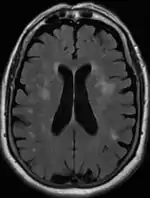

Head CT showing periventricular white matter lesions.

Leukoaraiosis is a particular abnormal change in appearance of white matter near the lateral ventricles. It is often seen in aged individuals, but sometimes in young adults.[1][2] On MRI, leukoaraiosis changes appear as white matter hyperintensities (WMHs) in T2 FLAIR images.[3][4] On CT scans, leukoaraiosis appears as hypodense periventricular white-matter lesions.[5]

The term "leukoaraiosis" was coined in 1986[6][7] by Hachinski, Potter, and Merskey as a descriptive term for rarefaction ("araiosis") of the white matter, showing up as decreased density on CT and increased signal intensity on T2/FLAIR sequences (white matter hyperintensities) performed as part of MRI brain scans.